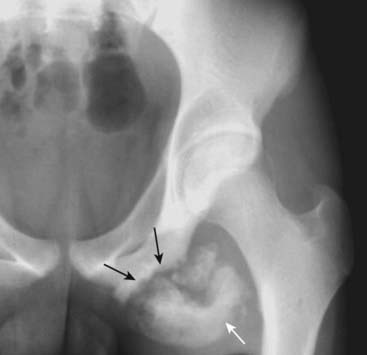

Figure 22-14 Slipped capital femoral epiphysis.

Slipped capital femoral epiphysis (SCFE) is a manifestation of a Salter-Harris type I injury. It occurs more often in taller and heavier teenage boys and produces inferior, medial, and posterior slippage of the proximal femoral epiphysis (solid black arrow) relative to the neck of the femur. A line drawn parallel to the neck of the femur (solid white lines) should intersect a portion of the head. It does so on the normal left side, but does not on the right side because the epiphysis has slipped.